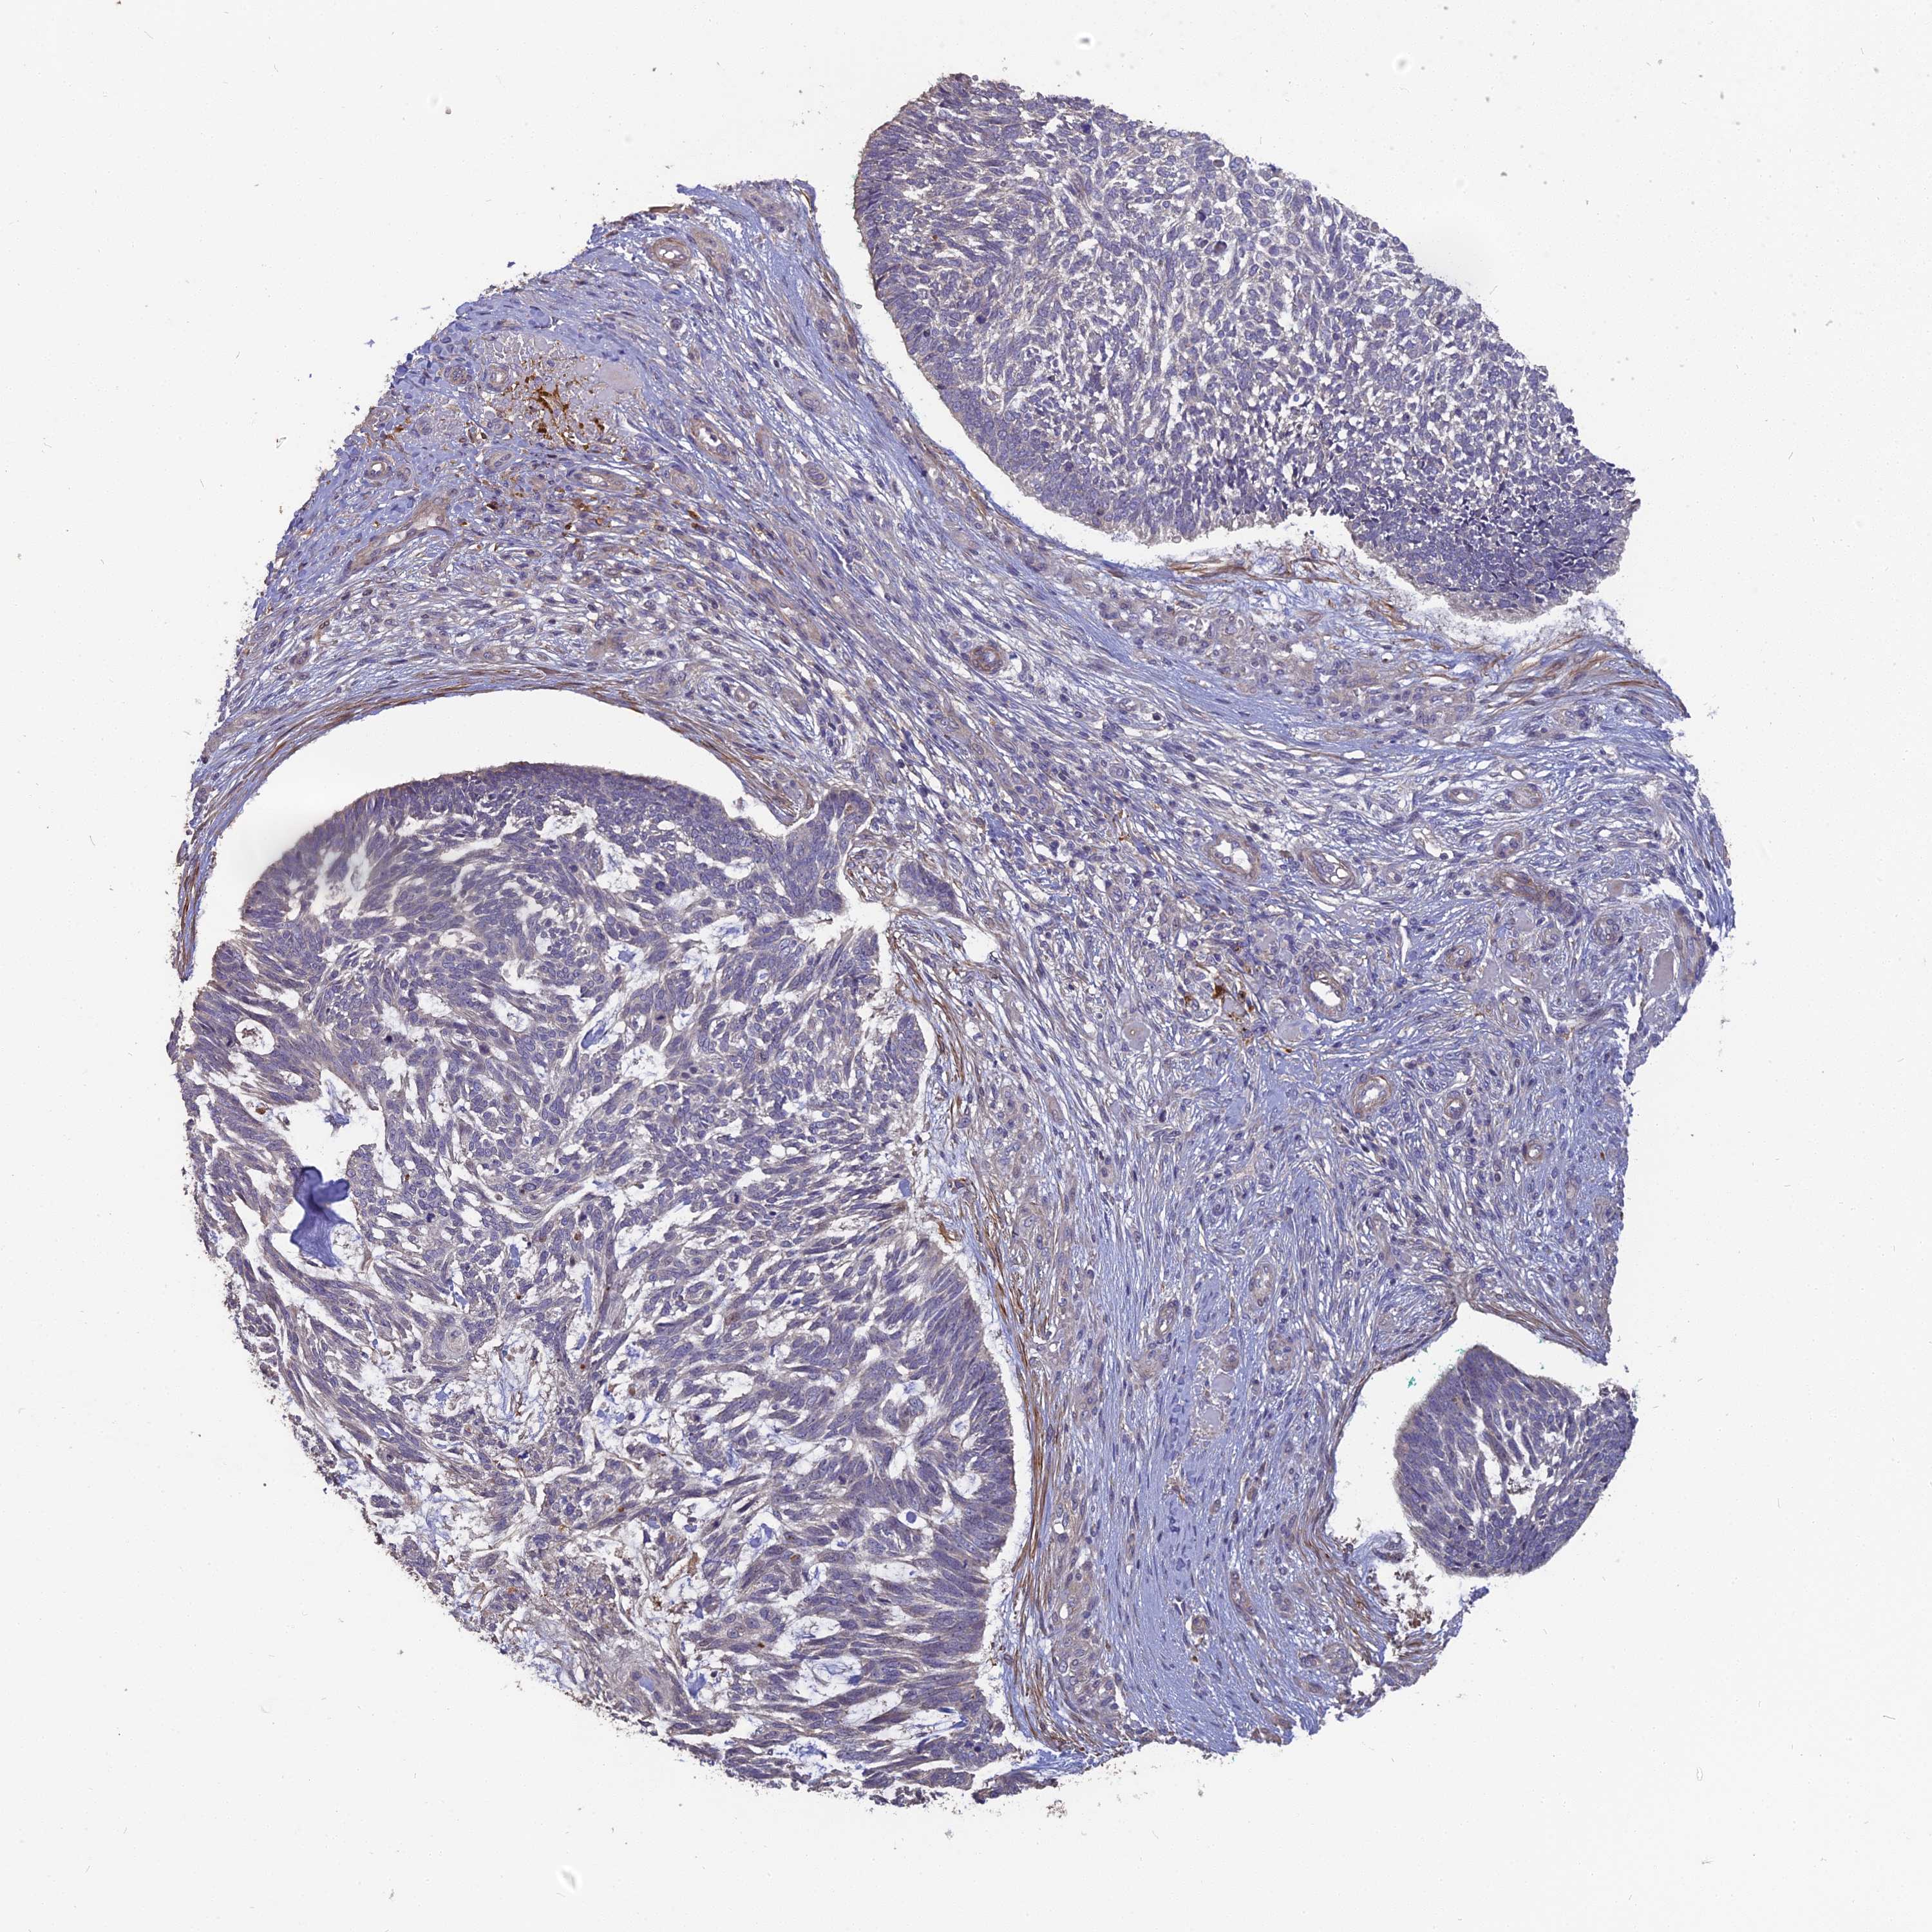

SKIN CANCER - Protein expressioni

A mouse-over function shows sample information and annotation data. Click on an image to view it in a full screen mode. Samples can be filtered based on level of antibody staining by selecting one or several of the following categories: high, medium, low and not detected. The assay and annotation is described here.

Each image is clickable and will lead to virtual microscopy that enables deeper exploration of all samples and also displays staining intensity scores, fraction scores and subcellular localization as well as patient and tissue information for each sample.

Antibody HPA042573

Squamous cell carcinoma, metastatic, NOS